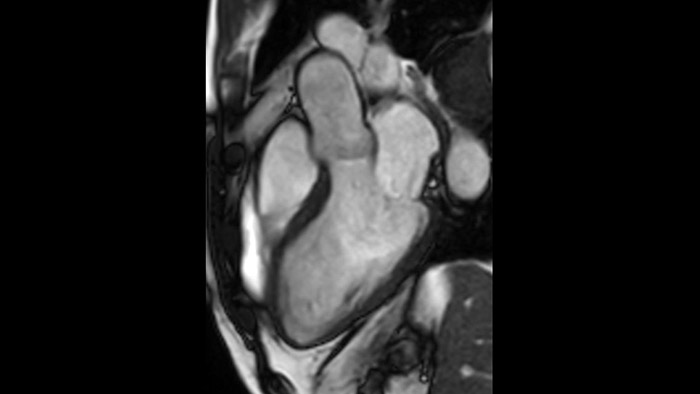

Due to the design of the BlueSeal magnet there is a negligible energy transfer from gradient coil to the magnet. This allows to maintain perfect B0 stability overtime which is especially beneficial for B0 sensitive acquisitions like cardiac bTFE sequences.

Addition of Compressed SENSE to your cardiac exams reduces the time spent in the MRI scanner for the patient and enables the reduction of breath hold times while maintaining virtually equal image quality4. Compressed SENSE is applicable to both 2D and 3D acquisitions.